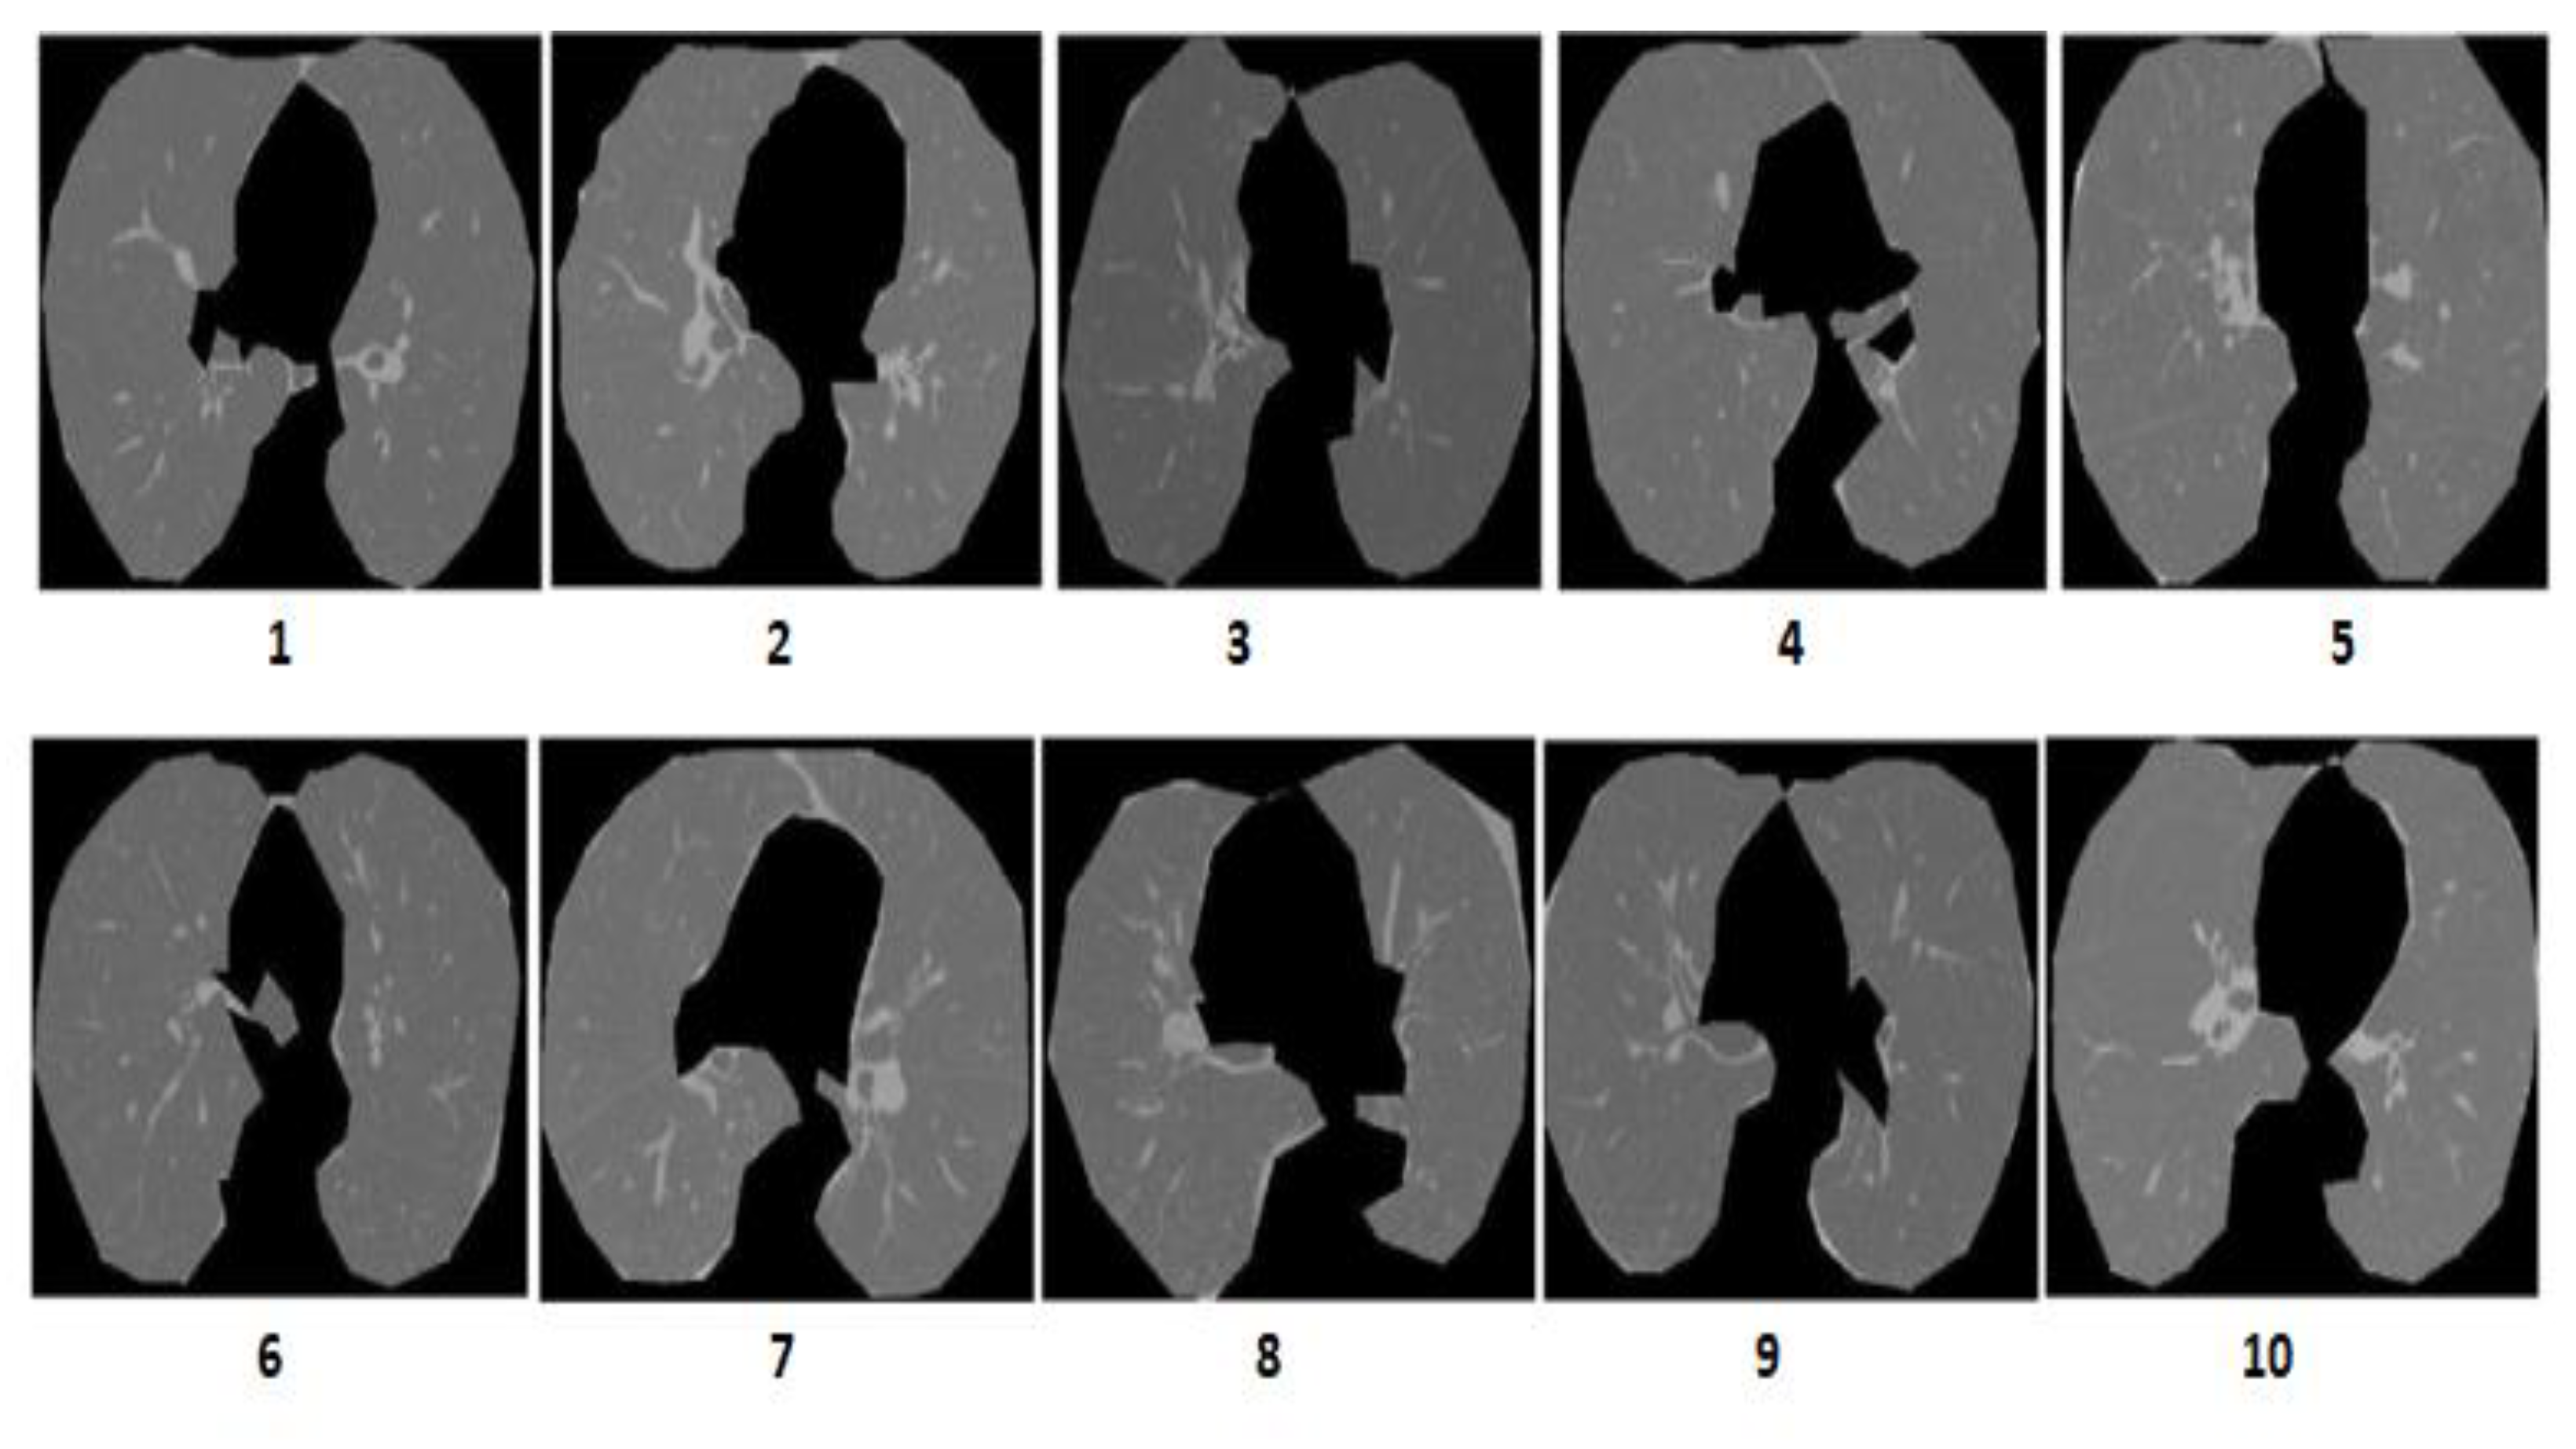

3.3. Performance on the I-ELCAP Database